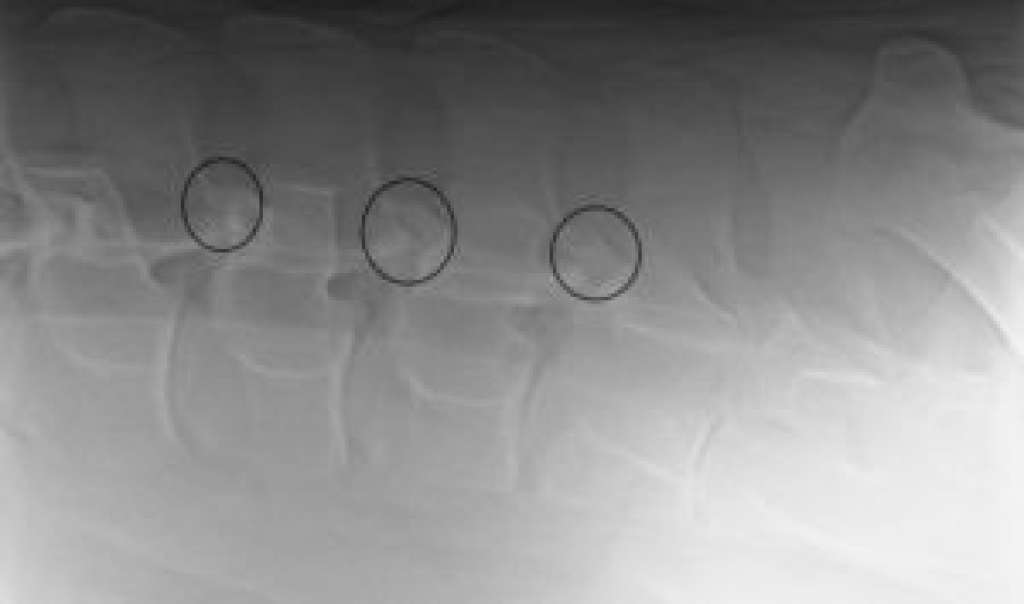

Links: Röntgenopname van de facetgewrichten van de lendenen

Rechts: Het omcirkelde facetgewricht vertoont botnieuwvorming ten gevolge van artrose

Röntgenopname van de facetgewrichten van de lendenen

Het omcirkelde facetgewricht vertoont botnieuwvorming ten gevolge van artrose